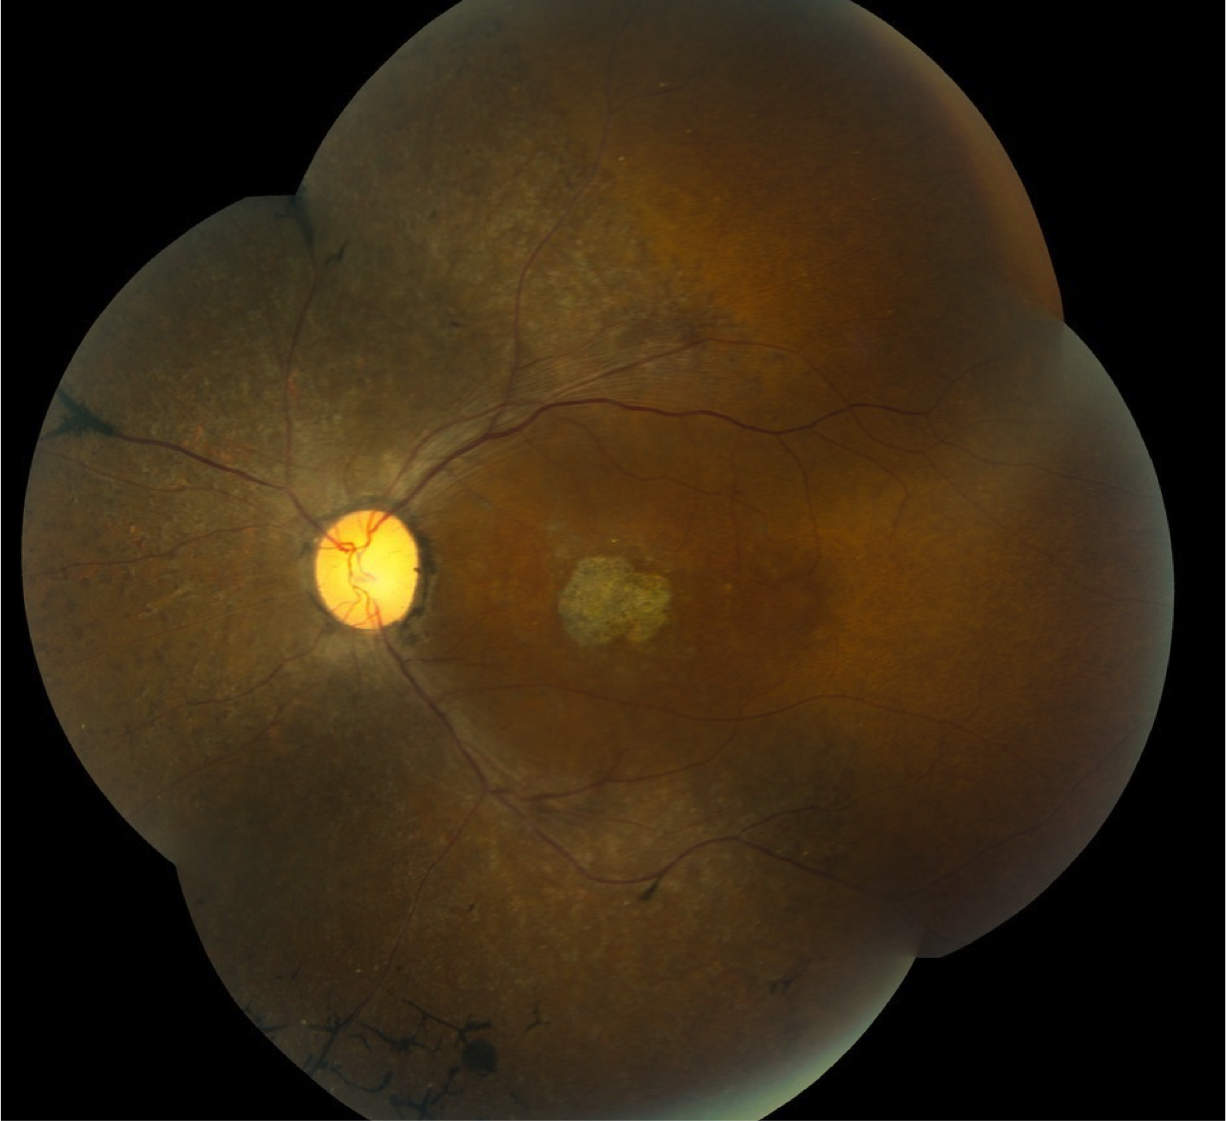

Case 2 is a 47 year old woman with 20/500 visual acuity. She had normal acuity before age 10 and her parents still have normal vision.

Color fundus photograph of the left eye.

This lady was born with an extra digit on the postaxial side of both hands and both feet and small scars can still be seen where these digits were removed. Her cognitive ability is a bit below normal and her body mass index is above normal. She also has type 2 diabetes mellitus.